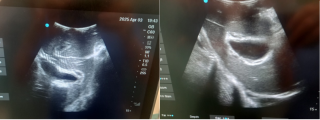

A 60 year old man presented with spoliative anemia. He is not known for cutanous macules around the mouth. An initial work up by colonoscopy and gastroscopy revealed a Helicobacter pylori infection without other significant abnormalities. Subsequently, a magnetic resonance imagery was performed and a 18 mm polyp located in the small intestine was identified (Figure 1). The lesion was not reachable by conventional endoscopy techniques. As endoscopic resection was not feasible, the patient underwent an explorative laparoscopy which enabled the discovery of a lesion in the terminal ileum coupled with an intussuception. The histopathological examinations demonstrated a pedunculated polypoid lesion, measuring 2 x 1.7 cm with a pedicle measuring 2.4 cm consistent with a Peutz-Jegher Syndrome (Figure 2 and Figure 3). Multidisciplinary meeting proposed genetic counselling and endoscopic follow up.